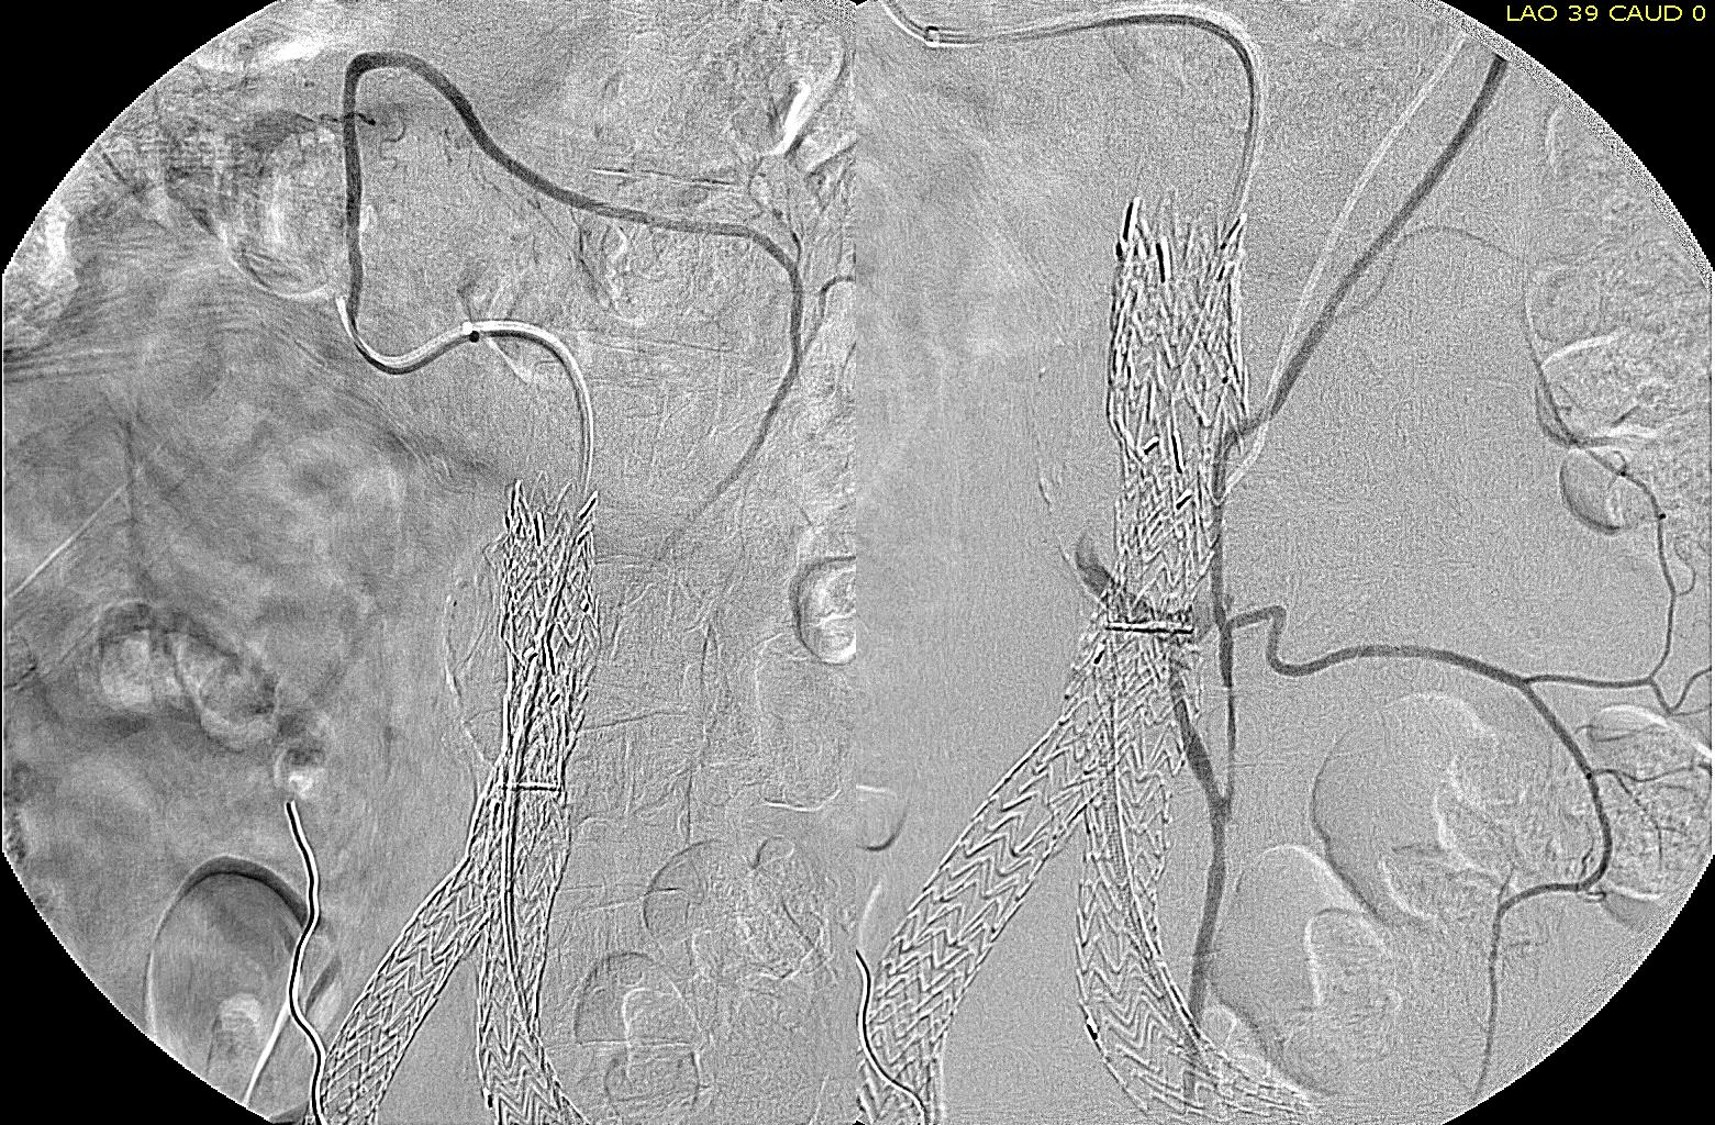

The patient had a successful EVAR or an eccentric infrarenal AAA which in followup grew due to the presence of a type II endoleak from the inferior mesenteric artery. This was seen on the CTA and duplex ultrasound. Planning for assessment and treatment involved analyzing the CTA in centerline, tracking the source of the arterial blood flow into the sac.

The centerline from the SMA into the middle colic artery shows a meandering but patent path via the Arc of Riolan to the left colic artery to the inferior mesenteric artery. In my experience this is straightforward to access selectively from the femoral approach, but it illustrates for the trainees the concept of building up access which I refer to as building the intervention machine.

The first step in the access involves getting stable footing in the SMA. Selective access can be performed with a shaped catheter, and once accessed, a Rosen wire is used to track in a curved long sheath. Parking this sheath in the proximal SMA forms the foundation of this machine. The next step is access into the middle colic artery.

The CTA is particularly helpful in identifying the middle colic on the 3DVR projection. Selection of this is straightforward with a an angle catheter which I place a Tuohy Borst connector. This is the second stage of the machine, because further access with 0.35guage wires and catheters could result in spasm. This second sheath access (the Tuohy turns the catheter into a sheath) of the middle colic allows for selective 0.18 gauge catheters and wires to make the final step to the IMA and the AAA.

The access machine concept is important for planning interventions. Every major branch or turn needs to be crossed by your ultimate access sheath, if you want to avoid having to arduously reaccess those points, and building up a telescoping layer of sheaths is very handy. Every interventional case is done at some distance away from the access point on the skin, and so some though has to be given to how you will build that machine.